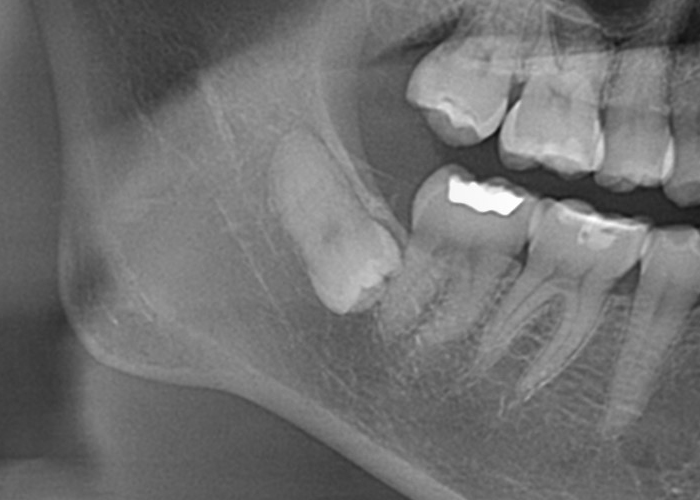

半埋伏智歯(部分的に露出している)

半埋伏とは、親知らずの一部が歯肉の下に埋まっており、一部が口腔内に露出している状態を指します。

露出している部分には、歯垢や食物がたまりやすくなり、炎症や感染、虫歯のリスクが高まる場合があります。

また、半埋伏の親知らずは、周囲の歯や歯肉に圧迫を与え、痛みや不快感を引き起こすこともあります。

さらに、半埋伏の親知らずが隣接する歯に対して圧力をかけることで、歯列の乱れや移動が起こる場合もあります。